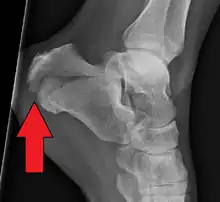

The Angle of Gissane, or "Critical Angle", is the angle formed by the downward and upward slopes of the calcaneal superior surface. On a lateral radiograph, an angle of Gissane > 130° suggests fracture of the posterior subtalar joint surface. Böhler's angle, or the "Tuber Angle", is another normal anatomic landmark seen in lateral radiographs. It is formed by the intersection of 1) a line from the highest point of the posterior articular facet to the highest point of the posterior tuberosity, and 2) a line from the former to the highest point on the anterior articular facet. Böhler's angle is normally 25° to 40°.[14] It is named after Austrian physician Lorenz Böhler.[16] A decreased angle is indicative of a calcaneal fracture.